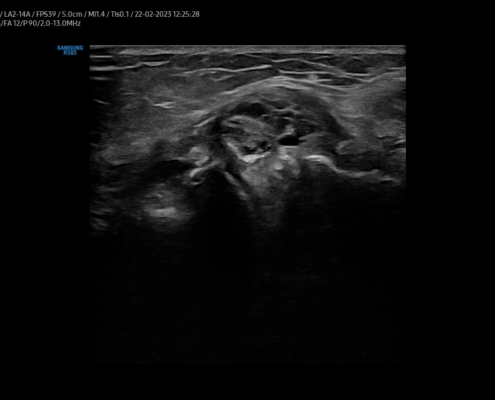

Bij het FysioHuis beoordelen we je knie met een vraaggesprek, lichamelijk onderzoek en echografie.

De meniscus kan je meestal niet goed genoeg beoordelen met echografie. Wel kunnen we indirecte tekenen zien die kunnen duiden op betrokkenheid van je meniscus. Ook bekijken we je knieholte op het ontstaan van een bakerse cyste -een zwelling in je knieholte die ontstaat op basis van problemen aan de meniscus of artrose.